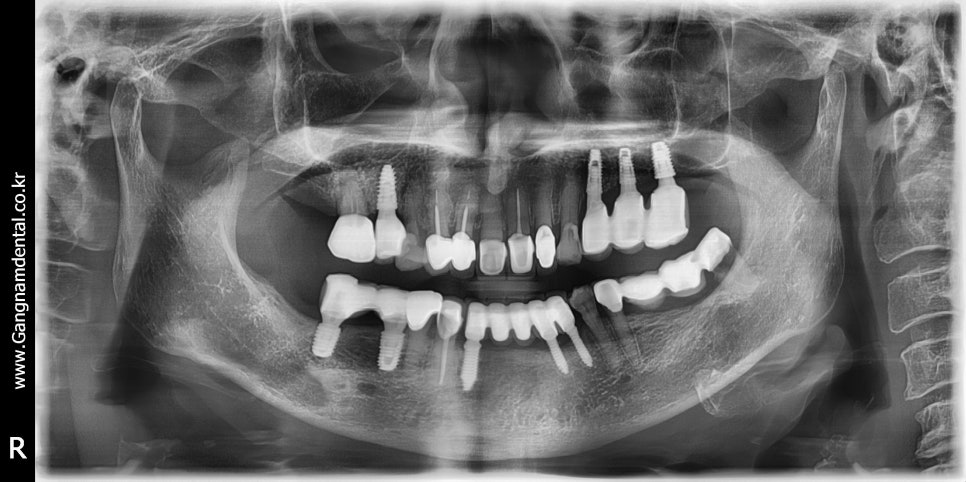

김영삼 원장님 라이브서저리 세미나에서 심은 내 첫 임플란트 케이스 (36i, 37i)

위 사진은 김영삼 원장님께 배운 기본기를 활용해서 심은 내 첫 임플란트 케이스인데, 물론 완벽하다고는 못하겠고 조금 아쉬움이 남기는 해도 처음 심는 임플란트치고 케이스 잘 골라서 잘 심었다고 칭찬도 들었다. 식립하고 정확히 세 달이 지나고는 보철도 올렸다.

아무튼 이 케이스에서 104p에 있는 깊이조절 테크닉을 사용했기 때문에 한 번 올려봤다. 아래 ppt 내용 중에 45도 각도로 토크랜치를 8번, 4번 사용했다는 말이 바로 원장님 책 104p에 적힌 내용을 활용한 것이다.